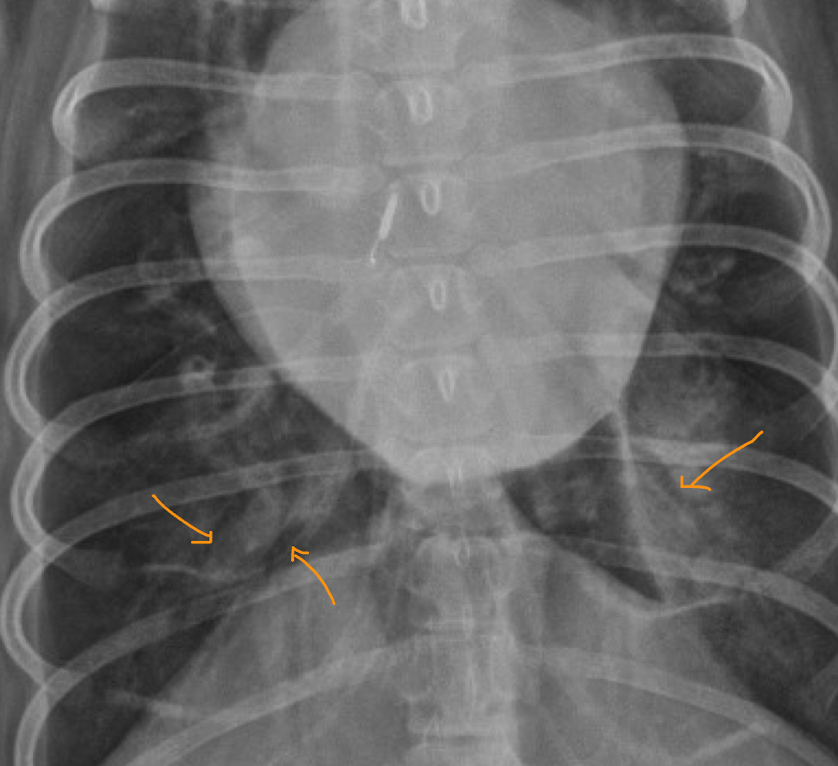

26

what is this outlining

pleural fissure lines pleural effusion- fluid dissects between the lung lobes at the normal anatomic boundaries